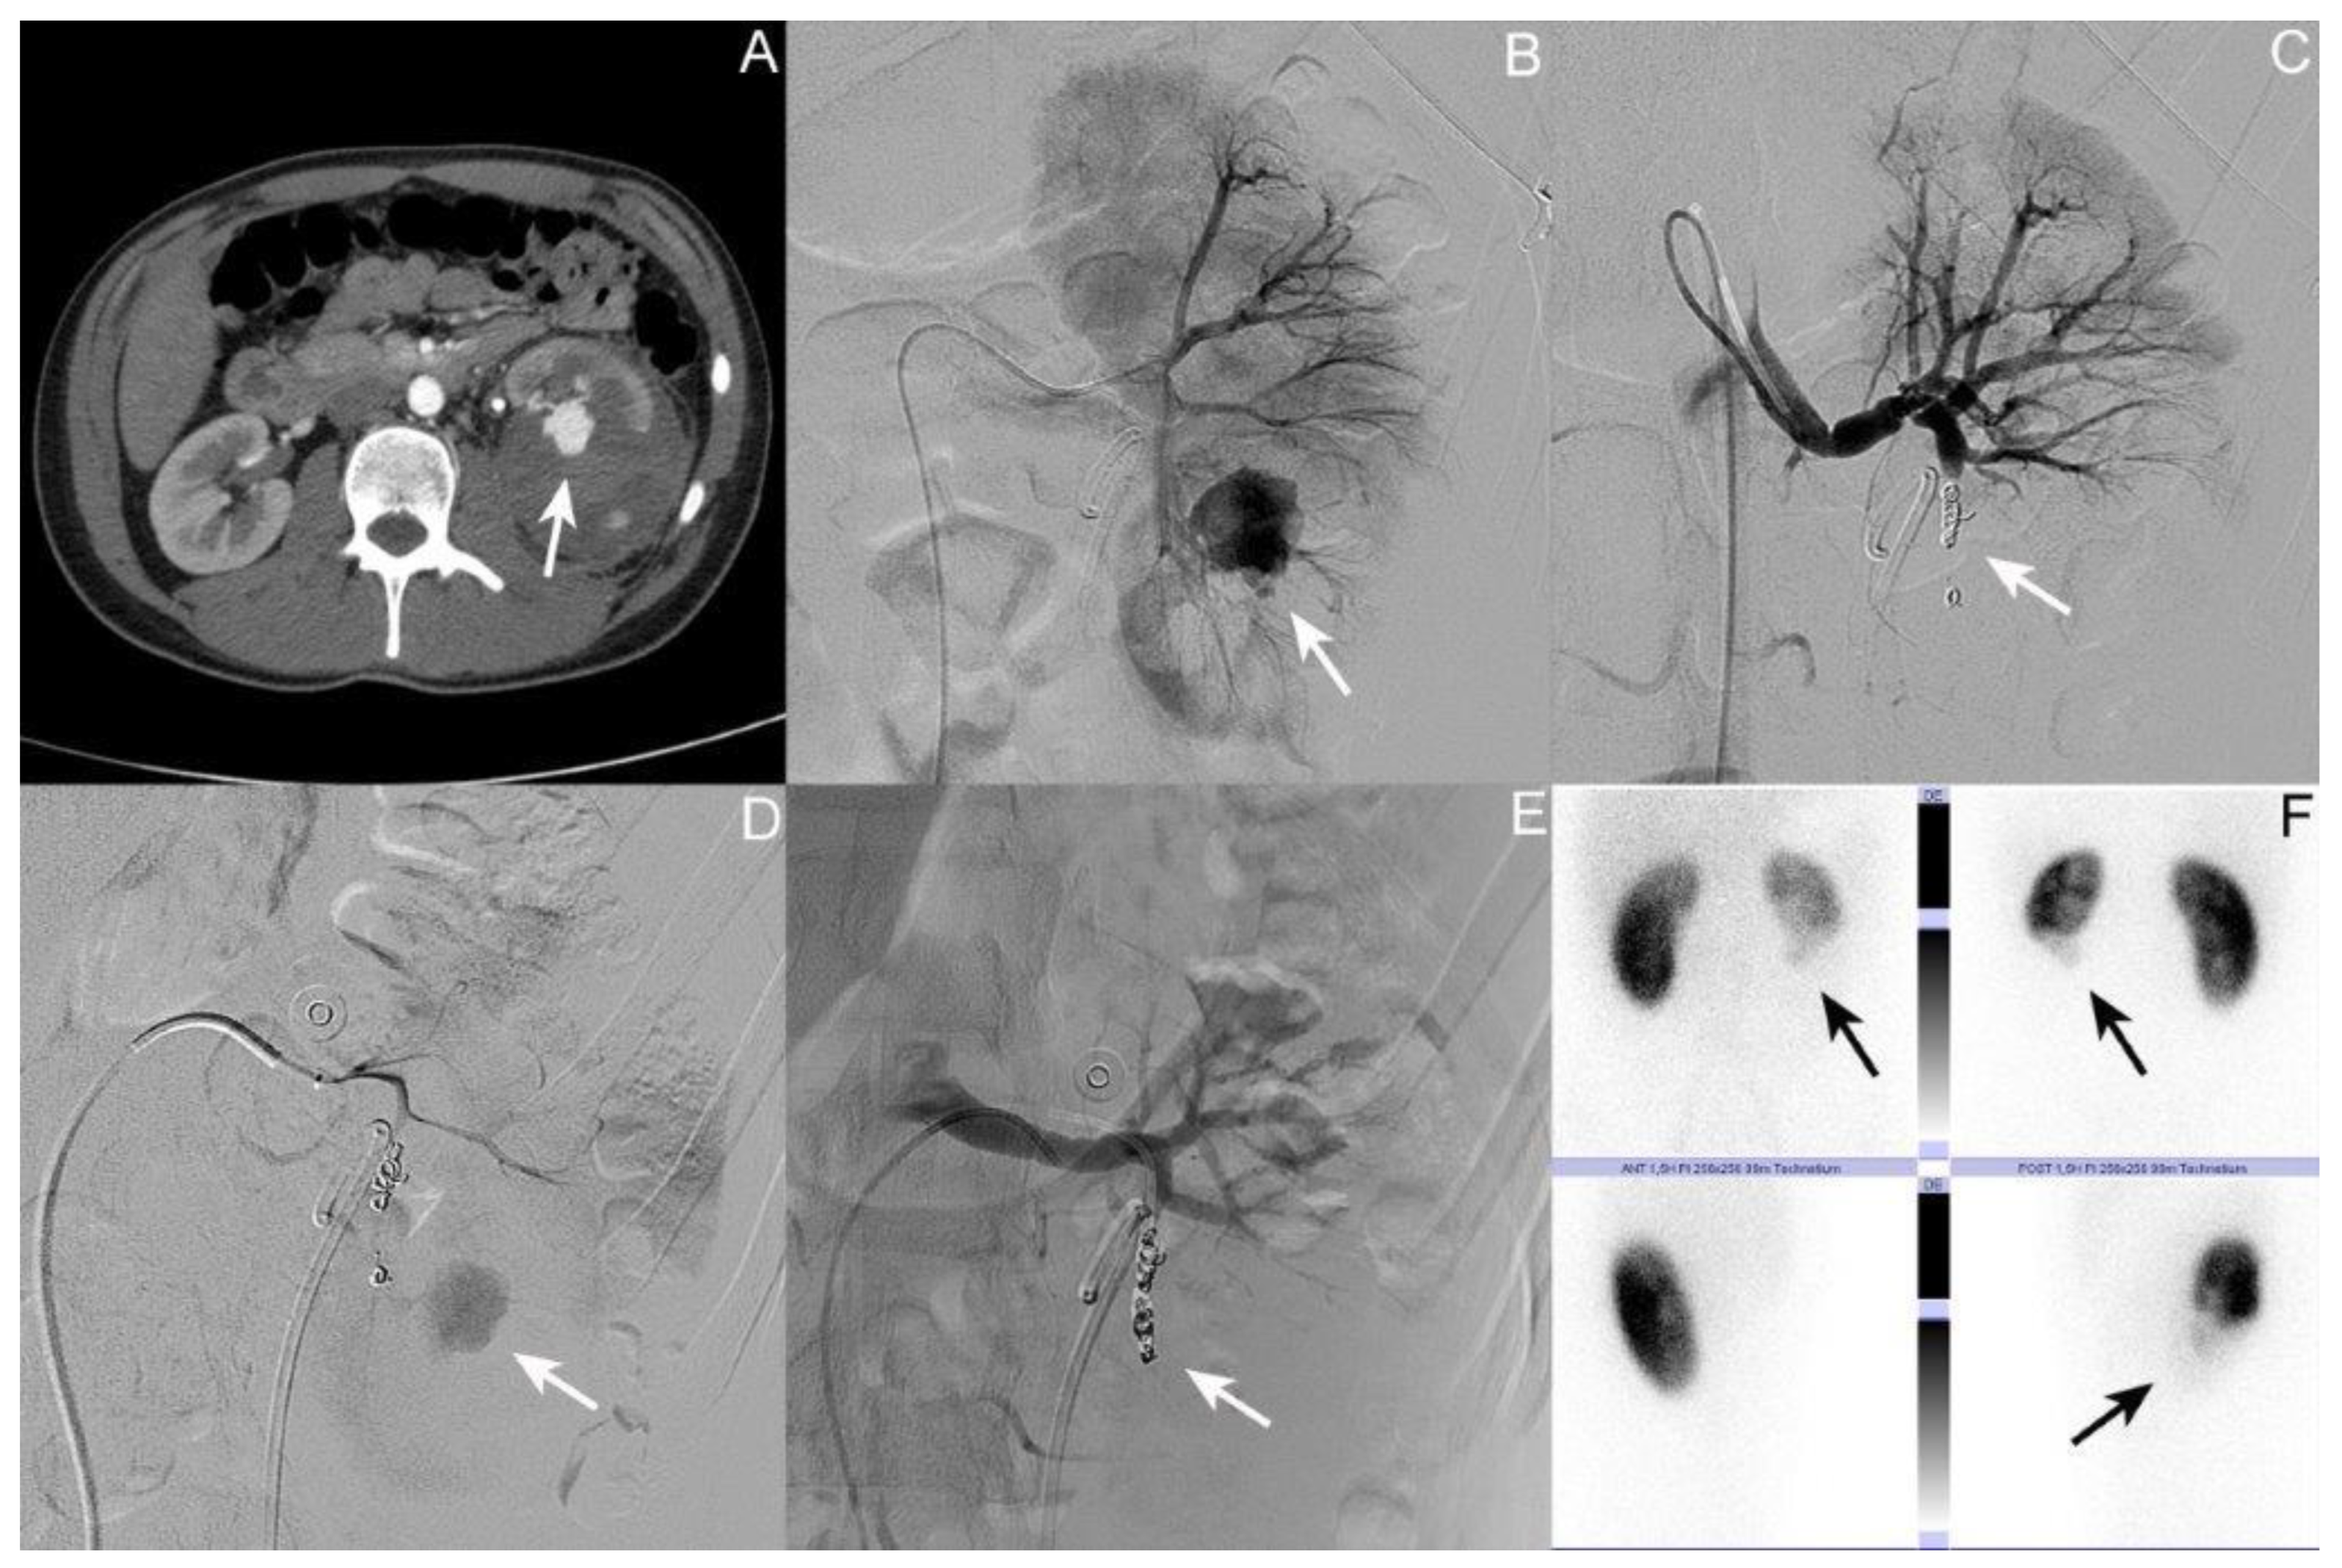

3.1. Patient I: Male Patient, Aged 17 Years

| Time of first diagnosis of AV fistula after the initial trauma in days | 13 | 1 | 7 | 7 |

| Size of AV fistula in mm | 24 | 12 | 20 | 18.7 |

| Time between trauma and onset of symptoms in days | 13 | 9 | NA | 11 |

| Symptoms | Flank pain, HU |

| Number of coil embolizations performed | 2 | 1 | 2 | 1.7 |

| Time of DMSA renal scintigraphy after the trauma in days | 248 | NA | 106 | 177 |

| Result of DMSA renal scintigraphy | -No TA in the lower kidney pole on the left side -Contribution: right/left kidney 65%:35% | NA | -No TA in the lower kidney pole on the right side -Contribution: left/right kidney 61%:39% |